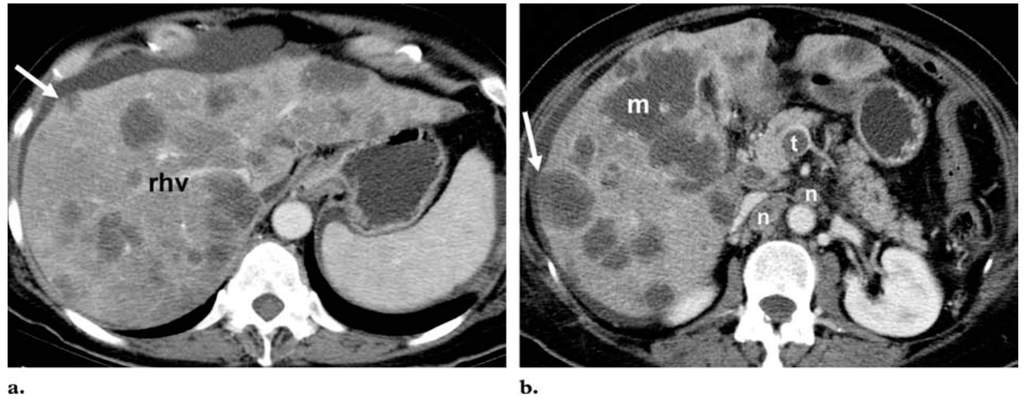

4. Hepatic Metastatic Disease